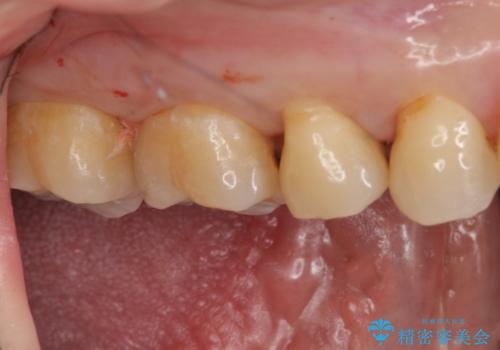

- 右上7 セラミックインレー 77000円×1本費用は治療当時の料金となります

セラミックインレー装着後は食べ物の詰まりも改善され、お掃除がしやすい環境になりとても満足していただけました。

奥歯は歯磨きが難しい上にご自身で状態を確認することが難しい場所になっています。

食べ物が詰まりやすいなどの症状が出ると虫歯が潜んでいる可能性が高いため、お悩みのある方はいつでもご相談ください。